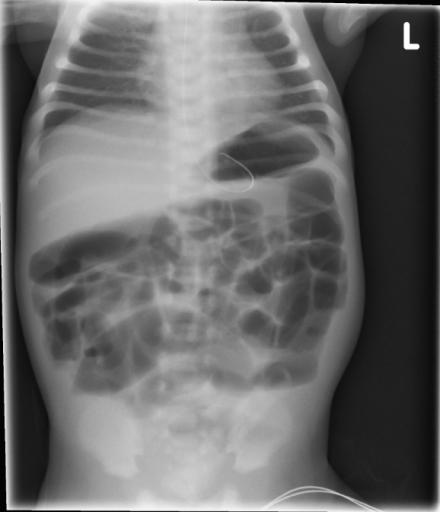

Нормы обзорной рентгенографии брюшной полости